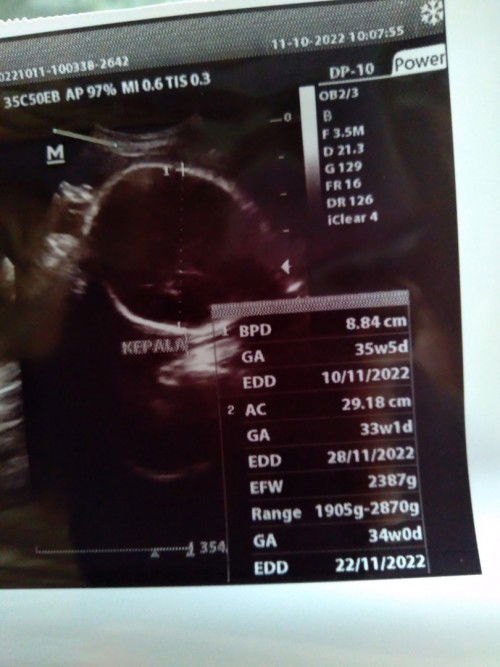

Baca lagiBpd itu lingkar kepala bayi nya ya bun. Klo di lihat dari ukuran kepala bayi nya uda 35w5d Kalo ac itu lingkar perut bayi bun. Nah disitu kalo di lihat lingkar perut nya sama dengan lingkar perut bayi uk 33w1d Klo edd nya ikutin yg hpht saja bun

Itu karena dokter ngecek satu satu, dari lingkar kepala, lingkar perut, panjang tulang kaki gituu, jadinya EDD nya beda beda